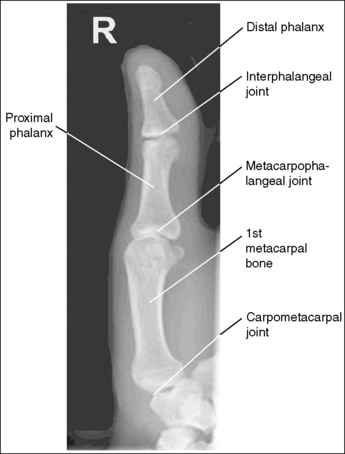

See Figures 4-12 and 4-13 and Box 4-5.

The first digit demonstrates an AP projection. The concavity on both sides of the phalangeal and metacarpal midshafts is equal, as is soft tissue width on both sides of the phalanges.

• An AP projection is accomplished by internally rotating the patient's hand until the thumb is positioned in an AP projection (Figure 4-14). The thumbnail can be used as a reference to determine when the thumb is truly placed in an AP projection. The nail should be positioned directly against the IR and should not be visible on either side of the thumb. A nonrotated AP thumb projection demonstrates equal concavity on both sides of the phalangeal and metacarpal midshafts, as well as equal soft tissue widths on both sides of the phalanges.

The IP, MP, and carpometacarpal (CM) joints are visible as open joint spaces, and the phalanges are not foreshortened.

The MP joint is at the center of the exposure field. The distal and proximal phalanges, the metacarpal, and the CM joint are included within the collimated field.

• Center a perpendicular central ray to the MP joint, which is located where the palm's interconnecting skin attaches to the thumb, to place it in the center of the image. Open the longitudinal collimation to include the distal phalanx and CM joint. Transversely collimate to within 0.5 inch (1.25 cm) of the thumb skin line.